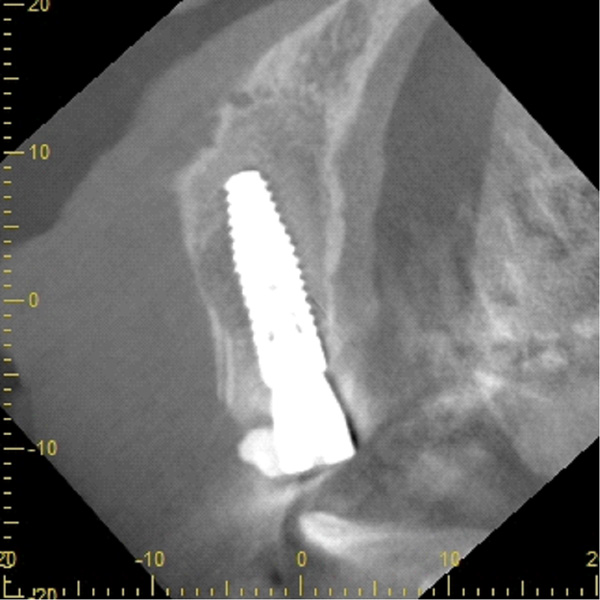

| 年代・性別 | 30代 女性 |

|---|---|

| 主訴 | 左上の乳歯がグラグラしてきた |

| 治療期間 | 約12ヶ月 |

| 費用 | 550,000円 |

| 治療内容 | インプラント、骨造成、セラミック修復 |

| 治療に伴うリスク | インプラント周囲炎 セラミックの破折、脱離 |